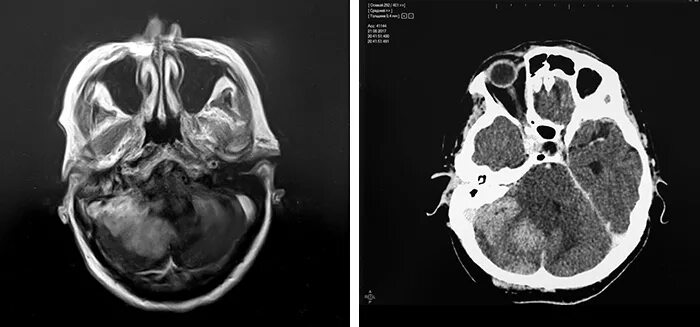

Кт и мрт